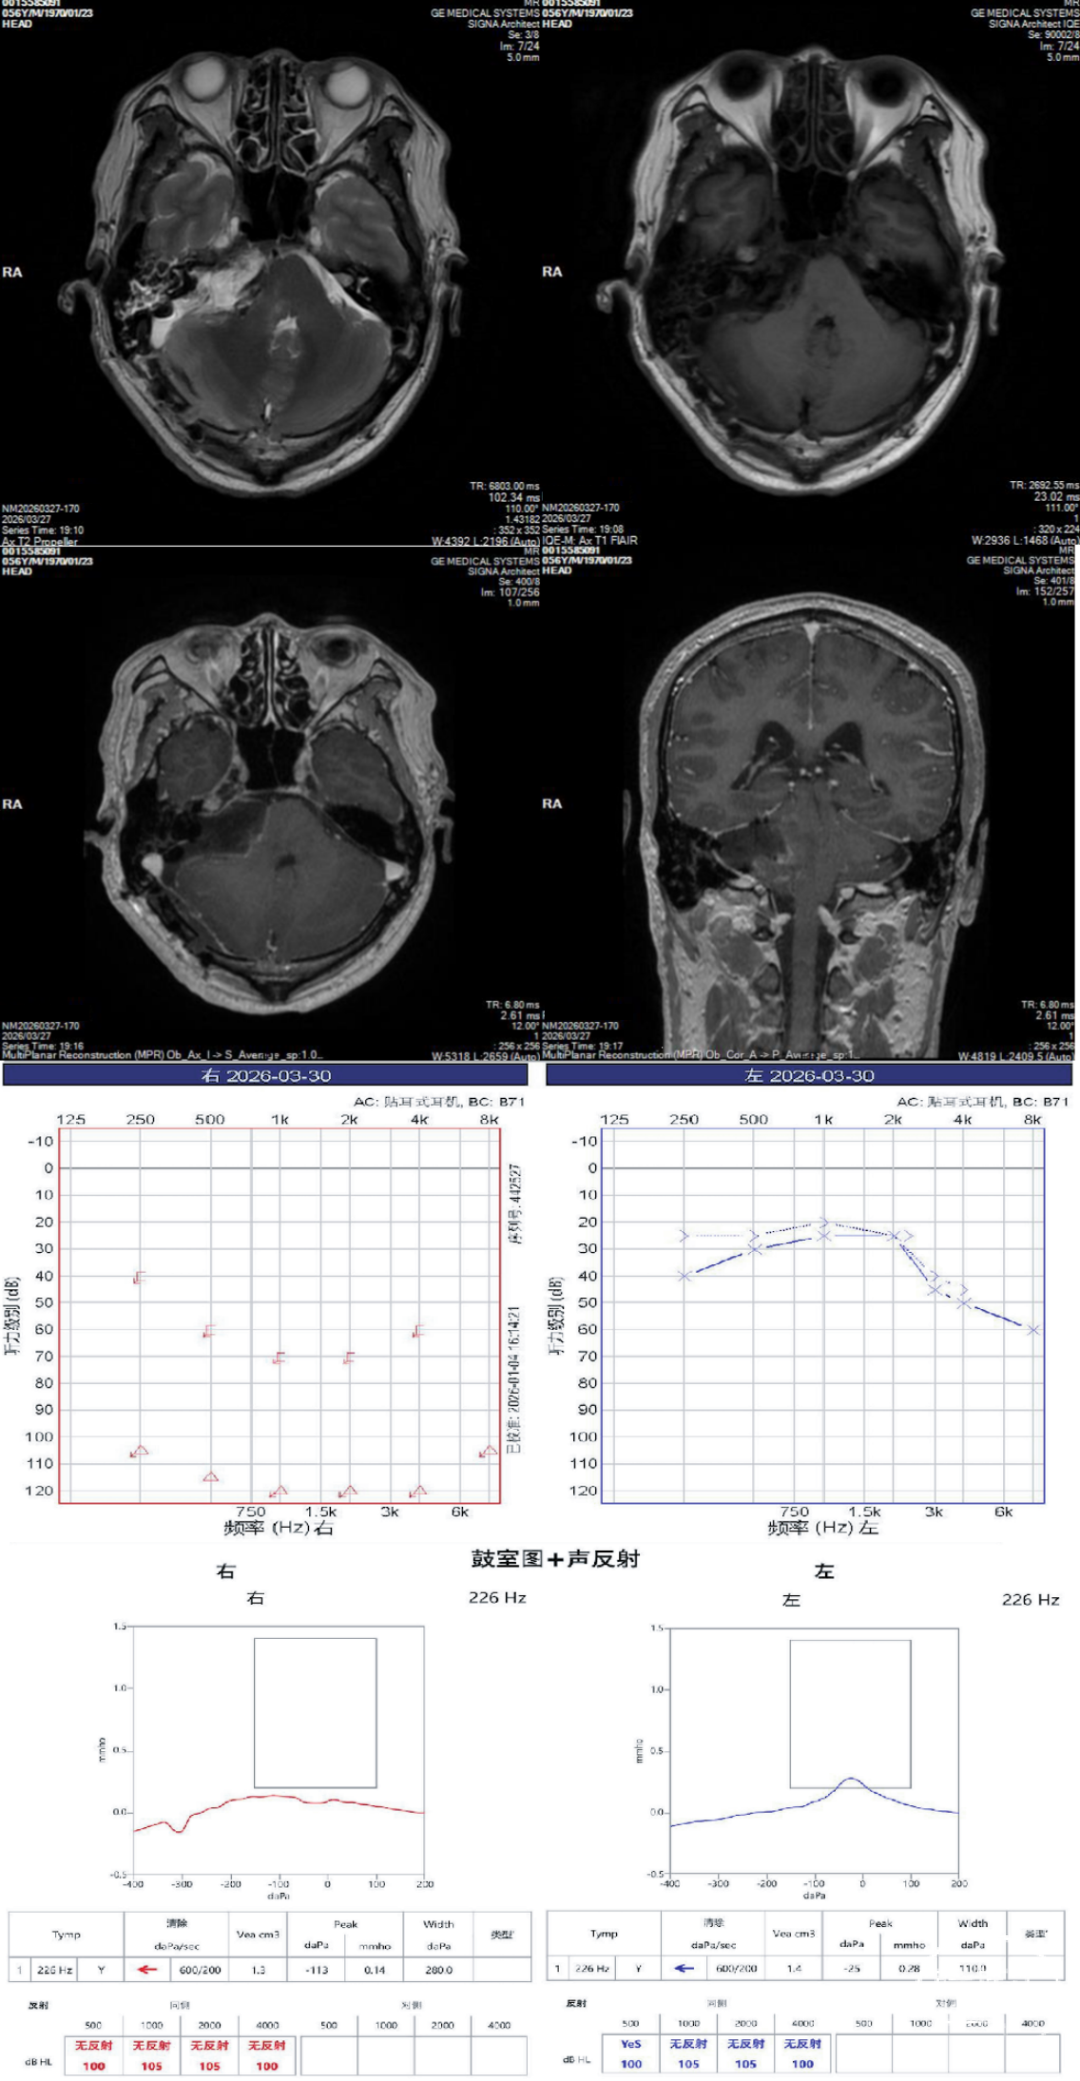

术前头部影像学资料示右侧桥小脑角区巨大占位,肿瘤呈多囊性改变,增强后不均匀强化,可见内听道扩大,病灶对脑干及小脑半球形成明显压迫,并继发脑积水。结合病灶位于CPA区、部分肿瘤伸入内听道、骨窗示内听道扩大等特点,术前高度考虑右侧听神经瘤。术前纯音测听提示听力明显受损;声导抗检查示双侧鼓室图基本为A型,右侧声反射减弱/缺失。

术前检查资料:

术后病理提示“(颅内)神经鞘瘤”,出院时患者一般情况可,神志清楚,语言流利,切口愈合良好,无红肿渗出,未诉明显特殊不适,无新发明显肢体功能障碍。术后纯音测听提示右耳听阈进一步升高,左耳听力相对保留;声导抗检查仍示鼓室图基本正常。

术后检查资料:

本例除面神经功能完整保留外,另一个值得讨论的话题在于患者整体听力的显著改善。患者术前已存在明显听力下降,但双侧电测听听阈分布几乎一致,患侧听力与健侧差异不大,考虑测试所得右耳结果为“盗听”所得。术中也证实右侧蜗神经结构明显扩张,表面水肿,神经纤维混乱。术后纯音测听提示右耳听阈进一步升高,说明尽管术中蜗神经在解剖上得以部分保留,但功能性保留仍较困难。这也是巨大听神经瘤治疗中的常见现实问题:当肿瘤体积巨大、长期压迫且与面听神经复合体粘连紧密时,解剖保留并不完全等同于功能保留。因此,对此类患者术前应充分沟通手术目标,明确以肿瘤安全切除、脑干减压及面神经保护为优先,听力保留则取决于肿瘤大小、术前听力基础及术中神经解剖条件。然而本例患者术前对侧听力同时受累,是由于右侧巨大占位严重挤压脑桥位移,间接导致对侧内耳门周围结构受压,术后对侧压迫解除,整体听力显著改善,生活质量明显提高。